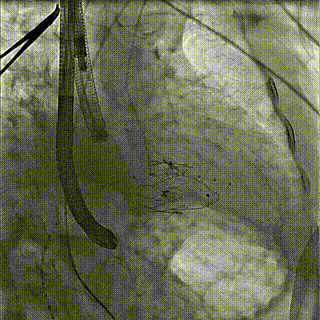

团队前期经过多次讨论,制定了周密的手术策略和预案。由于患者已是近九旬的超高龄老人,传统外科开胸手术风险极高,纯介入经血管三尖瓣替换能够明显减少创伤。术中陈茂及冯沅教授结合体表定位在造影指示下精准穿刺右侧颈静脉并预置两把血管缝合器。成功建立经皮血管入路后在食道超声和DSA的引导下顺利完成人工瓣膜植入,术后超声和造影显示人工三尖瓣同轴性良好,瓣架固定牢靠,无反流和瓣周漏,平均跨瓣压差降为1mmHg。术毕收紧预置的血管缝合器缝线完成止血,缝合效果满意,在手术室即刻拔除气管插管。

术前DSA造影